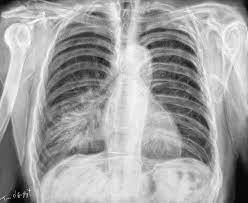

Legionellose Radio Pulmonaire : 1 / Il peut être localisé à une partie du poumon ou s'étendre à l'ensemble de l'appareil pulmonaire.

Face aux symptômes qui évoquent une pneumopathie interstitielle, le médecin va tout d'abord prescrire une radio des poumons, qui met en évidence un épaississement du tissu interstitiel.